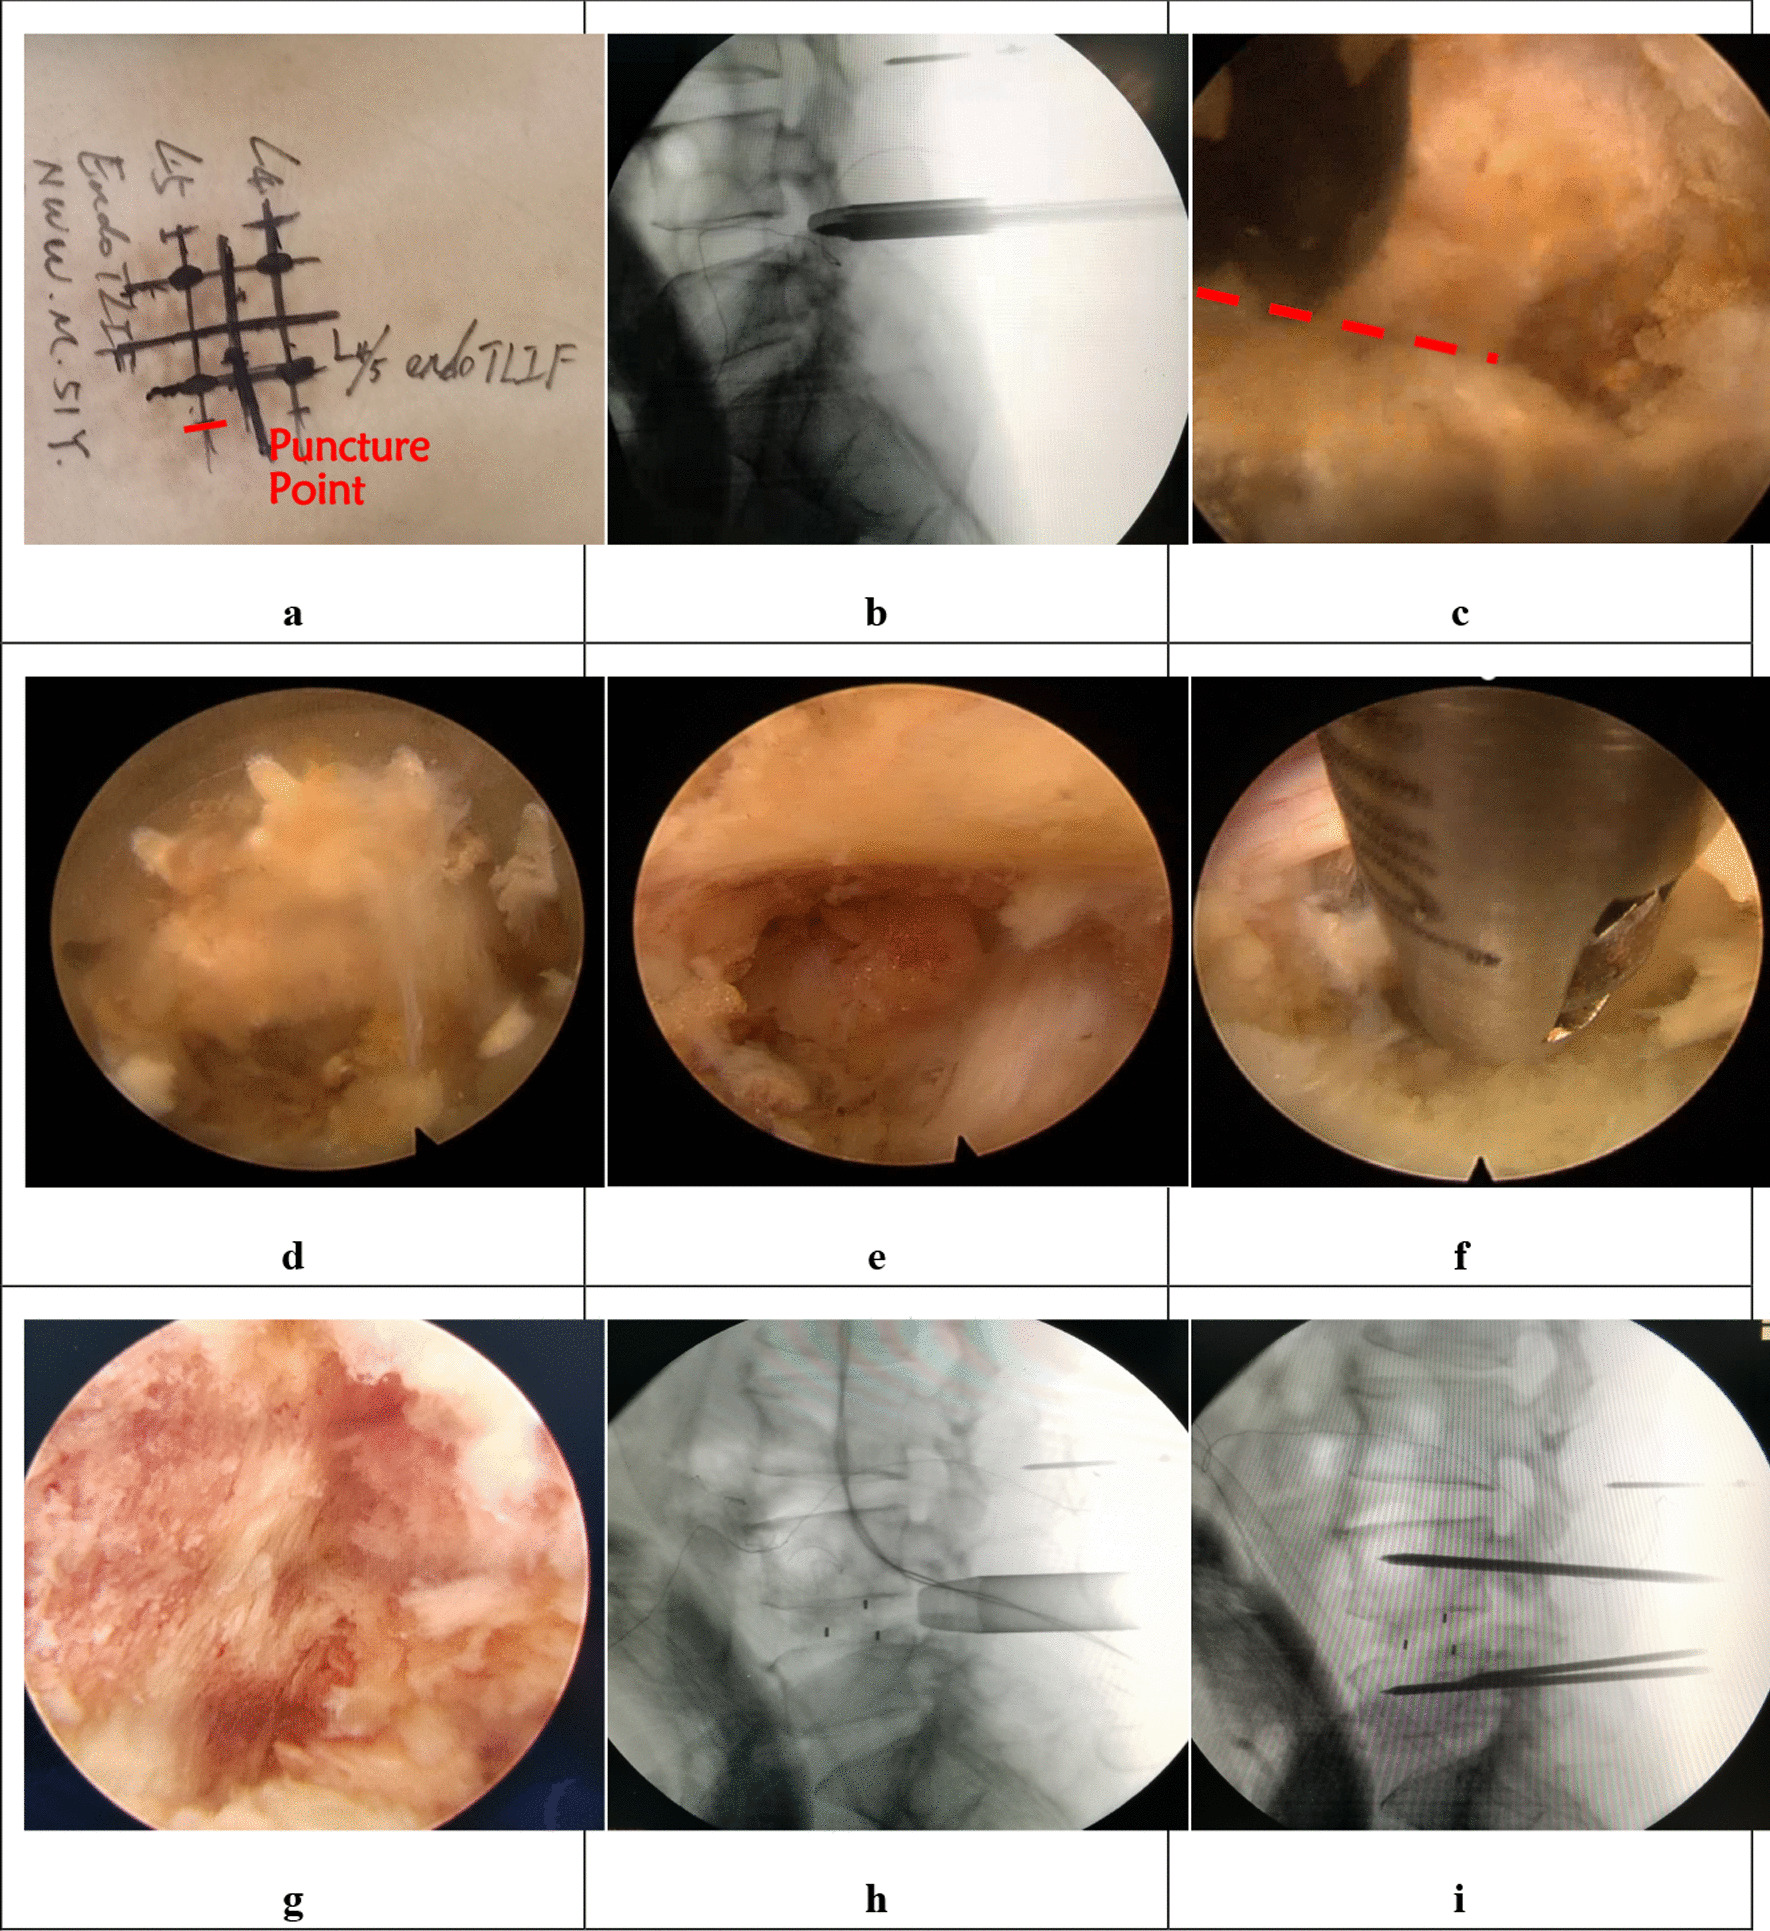

Fig. 3.

The combined figures show the steps of BLIF. a Guide wires’ insertion. b Soft tissue detachment. c Exposure of the superior margin of the L5 lamina (black arrow), interlaminar space and inferior edge of L4 lamina (white arrow). d Laminotomy. e Preparation of the bone graft bed with an endoscopic cobber. f Observation of bony bleeding sites. g The cage is seen through the endoscope. h The cage is justified in a transverse orientation with an impactor. i The correct location is confirmed under C-arm guidance